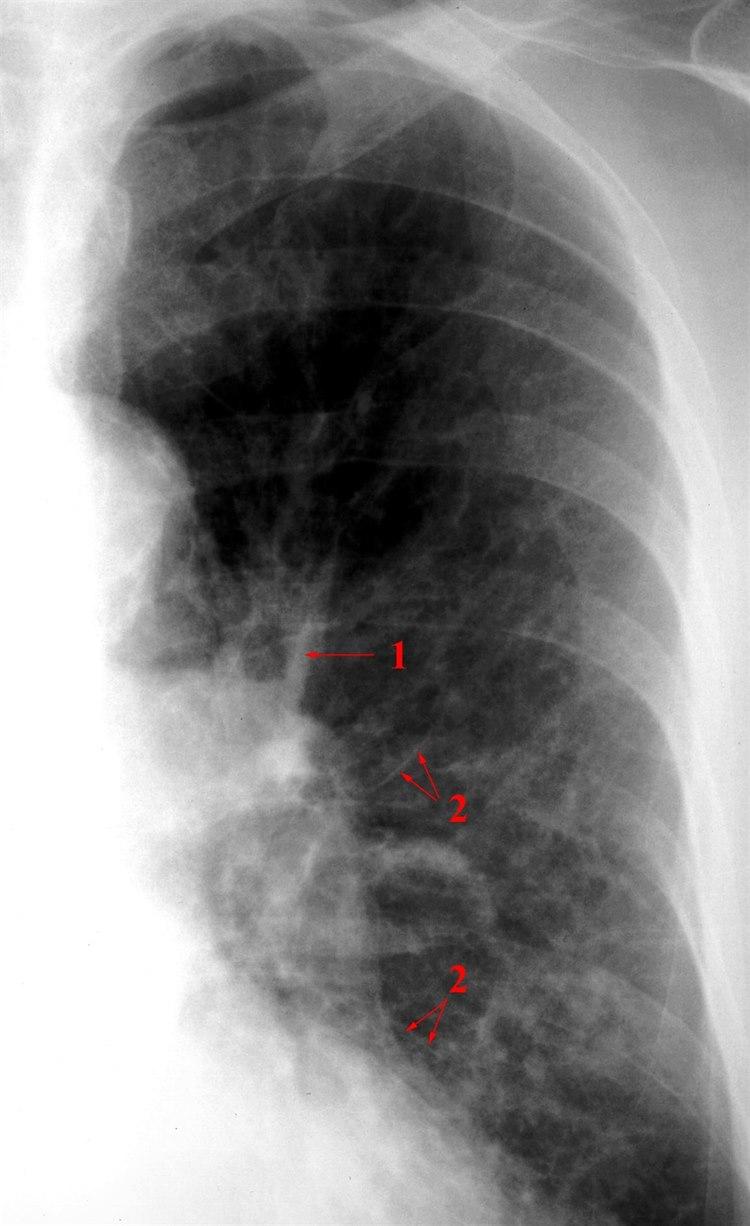

Litt vide lungekartegninger (1) og markerte interstitielle septa (2) på grunn av øket væskemengde i blodårene.